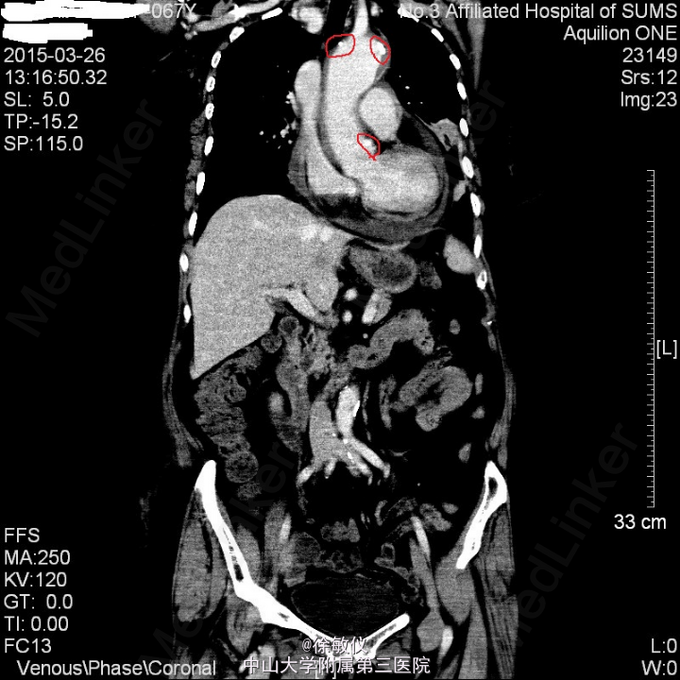

于急诊输液、止呕治疗后呕吐停止,胸闷持续3小时后症状减轻,予阿司匹林、氯吡格雷、立普妥负荷量口服后收入我科。 入院后查胸部、腹部ct发现有主动脉夹层。 诊断:冠状动脉粥样硬化性心脏病;主动脉夹层。

讨论:典型的急性主动脉夹层病人往往表现为突发的、剧烈的、胸背部、撕裂样疼痛。严重的可以出现心衰、晕厥、甚至突然死亡。该患者仅表现为胸闷,症状不典型。